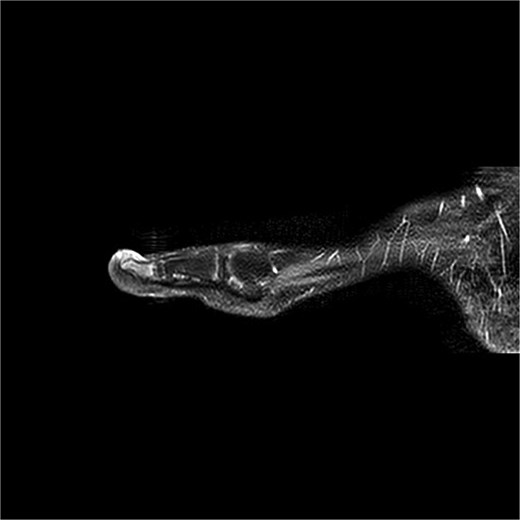

A 14-year-old female presented with recurrent SE of the right great toe (Fig. 4). She had a history of osteomyelitis in the same location, treated successfully before SE developed. MRI confirmed recurrence with underlying osteomyelitis (Fig. 6). Surgery was performed 2 days later (Fig. 5). Bone cultures revealed Staphylococcus sciuri, Staphylococcus caprae, and Staphylococcus warneri, with sparse growth in all five samples. She transitioned to oral dicloxacillin after 1 week of intravenous therapy. At 16 days, she was asymptomatic, and a 3-month follow-up was scheduled.

Preoperative MRI from case 2 demonstrating SE and associated bone marrow edema.